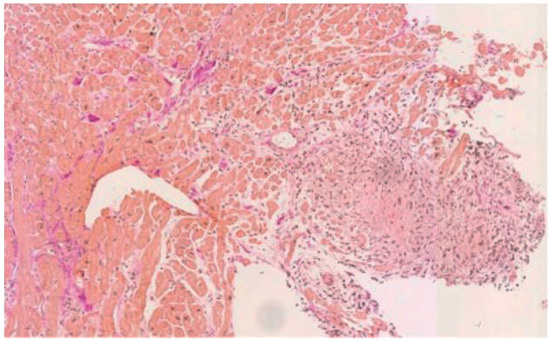

Cardiac Sarcoidosis with Coeliac Disease

by Stéphane Fournier, Julien Regamey, Samuel Rotman, Etienne Pruvot and Roger Hullin

Cardiovasc. Med. 2016, 19(4), 128; https://doi.org/10.4414/cvm.2016.00412 - 20 Apr 2016

This case of cardiac sarcoidosis started with manifestation of a complete atrioventricular block in a 42-year-old female without other cardiac dysfunction. Two years later, the patient presented with acute heart failure symptoms at the Emergency Department. Echocardiography at admission showed thinning and hyperdensity [...] Read more.

This case of cardiac sarcoidosis started with manifestation of a complete atrioventricular block in a 42-year-old female without other cardiac dysfunction. Two years later, the patient presented with acute heart failure symptoms at the Emergency Department. Echocardiography at admission showed thinning and hyperdensity of the basal interventricular septum, which is a rare but typical echocardiographic sign of cardiac sarcoidosis. Endomyocardial biopsy, positron emission tomography–computed t omography and transbronchial biopsy confirmed the clinical suspicion of sarcoidosis. Of note, the patient also had coeliac disease, which can occur conjointly with sarcoidosis. After 5 months of immunosuppressive treatment with methylprednisolone and azathioprine the burden of inflammatory lesions was significantly reduced and the patient had improved to New York Heart Association class I. Full article